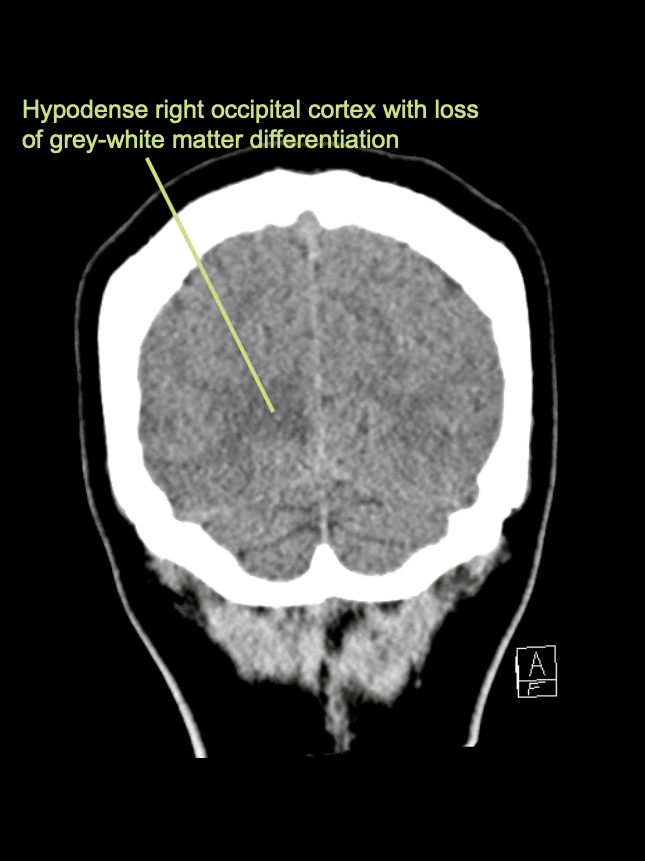

A 40-year-old female, presents with headache and abrupt left sided visual disturbance. She has a history of T2DM and hypertension.

On examination she has a left homonymous hemianopia.

There is an area of hypodensity and loss of grey-white matter differentiation within the right occipital lobe in keeping with a cortical infarct.

This represents a right PCA territory infarct.